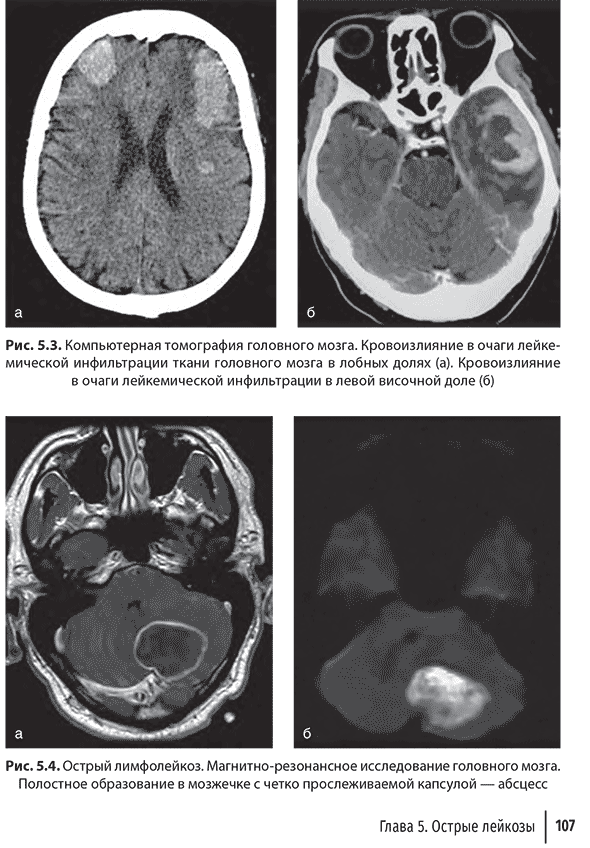

Глава 5. Острые лейкозы

и лечении острых лейкозов